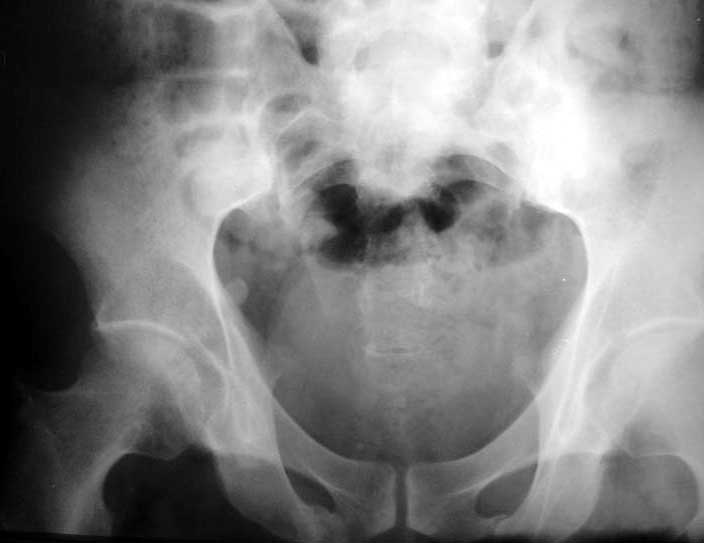

ФасInlet

Больной 64 лет, работник тяжелого физического труда, 29.10.02 на производстве получил удар трубой по переднему отделу таза. 2 месяца постельного режима, с 4 месяцев ходит с тростью. Беспокоят тянущие боли в нижних конечнстях при нагрузке, периодически ночные боли, хромота, постоянно припимает анальгетики. Снимки прилагаются. Виден подвывих в правом крестцово-подвздошном сочленении. Как лучше помочь пациенту? Заранее спасибо.

Alternating single leg stance AP pelvic films ("flamingo views") may be helpful to identify hemipelvic instability.

Based on the CT images you provided, he appears to have a nonunion of the the right ischium, which would explain his symptoms. General principles of treatment of hypertrophic (which this appears to be) nonunions suggest rigid fixation, but I'm not sure what the best approach would be. Could get a lag screw across the fracture through a Kocher-Langenbeck approach or plate osteosynthesis through direct ischial approach, but perhaps Chip, Adam or someone with more pelvic fracture experience could enlighten us all.

I think this is just a pelvic ring disruption that has gone on to a non-union. The arrow is pointing to the inferior ramus non-union, and

the sup ramus is a high "root" fracture, right near the pecten. The sup ramus fracture enters the tab - you could call it an acetabular

fracture - but down here in Dallas we treat these acutely as stable pelvic ring injuries. The fracture in the anterior portion of the

acetabulum is so low it doesn't seem to cause much trouble.

His R sacroiliac joint is opened anteriorly a little bit - the "unreduced posterior lesion" Alex mentioned in his first post. My earlier post about plating, bone grafting, etc., is all wrong.

Речь идёт о коплексном двустороннем повреждении таза с нарушением тазового кольца.

А именно: разрыв илио-сакрального сочленения справа, на этой же стороне трансацетабулярный перелом с незначительным смещением, перелом подвздошной кости слева. Исходя из вышеперечисленного, меня не удивляют двусторонние жалобы пациента. Однако, учитывая представленные снимки ЯМР и времени, прошедшим с момента травмы мне представляется пока преждевременным говорить об образовании ложных суставов. Судя по развиввшейся костной мозоли в области вышеперечисленных очагов, все переломы находяться в стадии консолидации. Вполне возможно, однако, что трансацетабулярный перелом приведёт в дальнейшем к развитию посттравматического артроза ТБ- сустава.